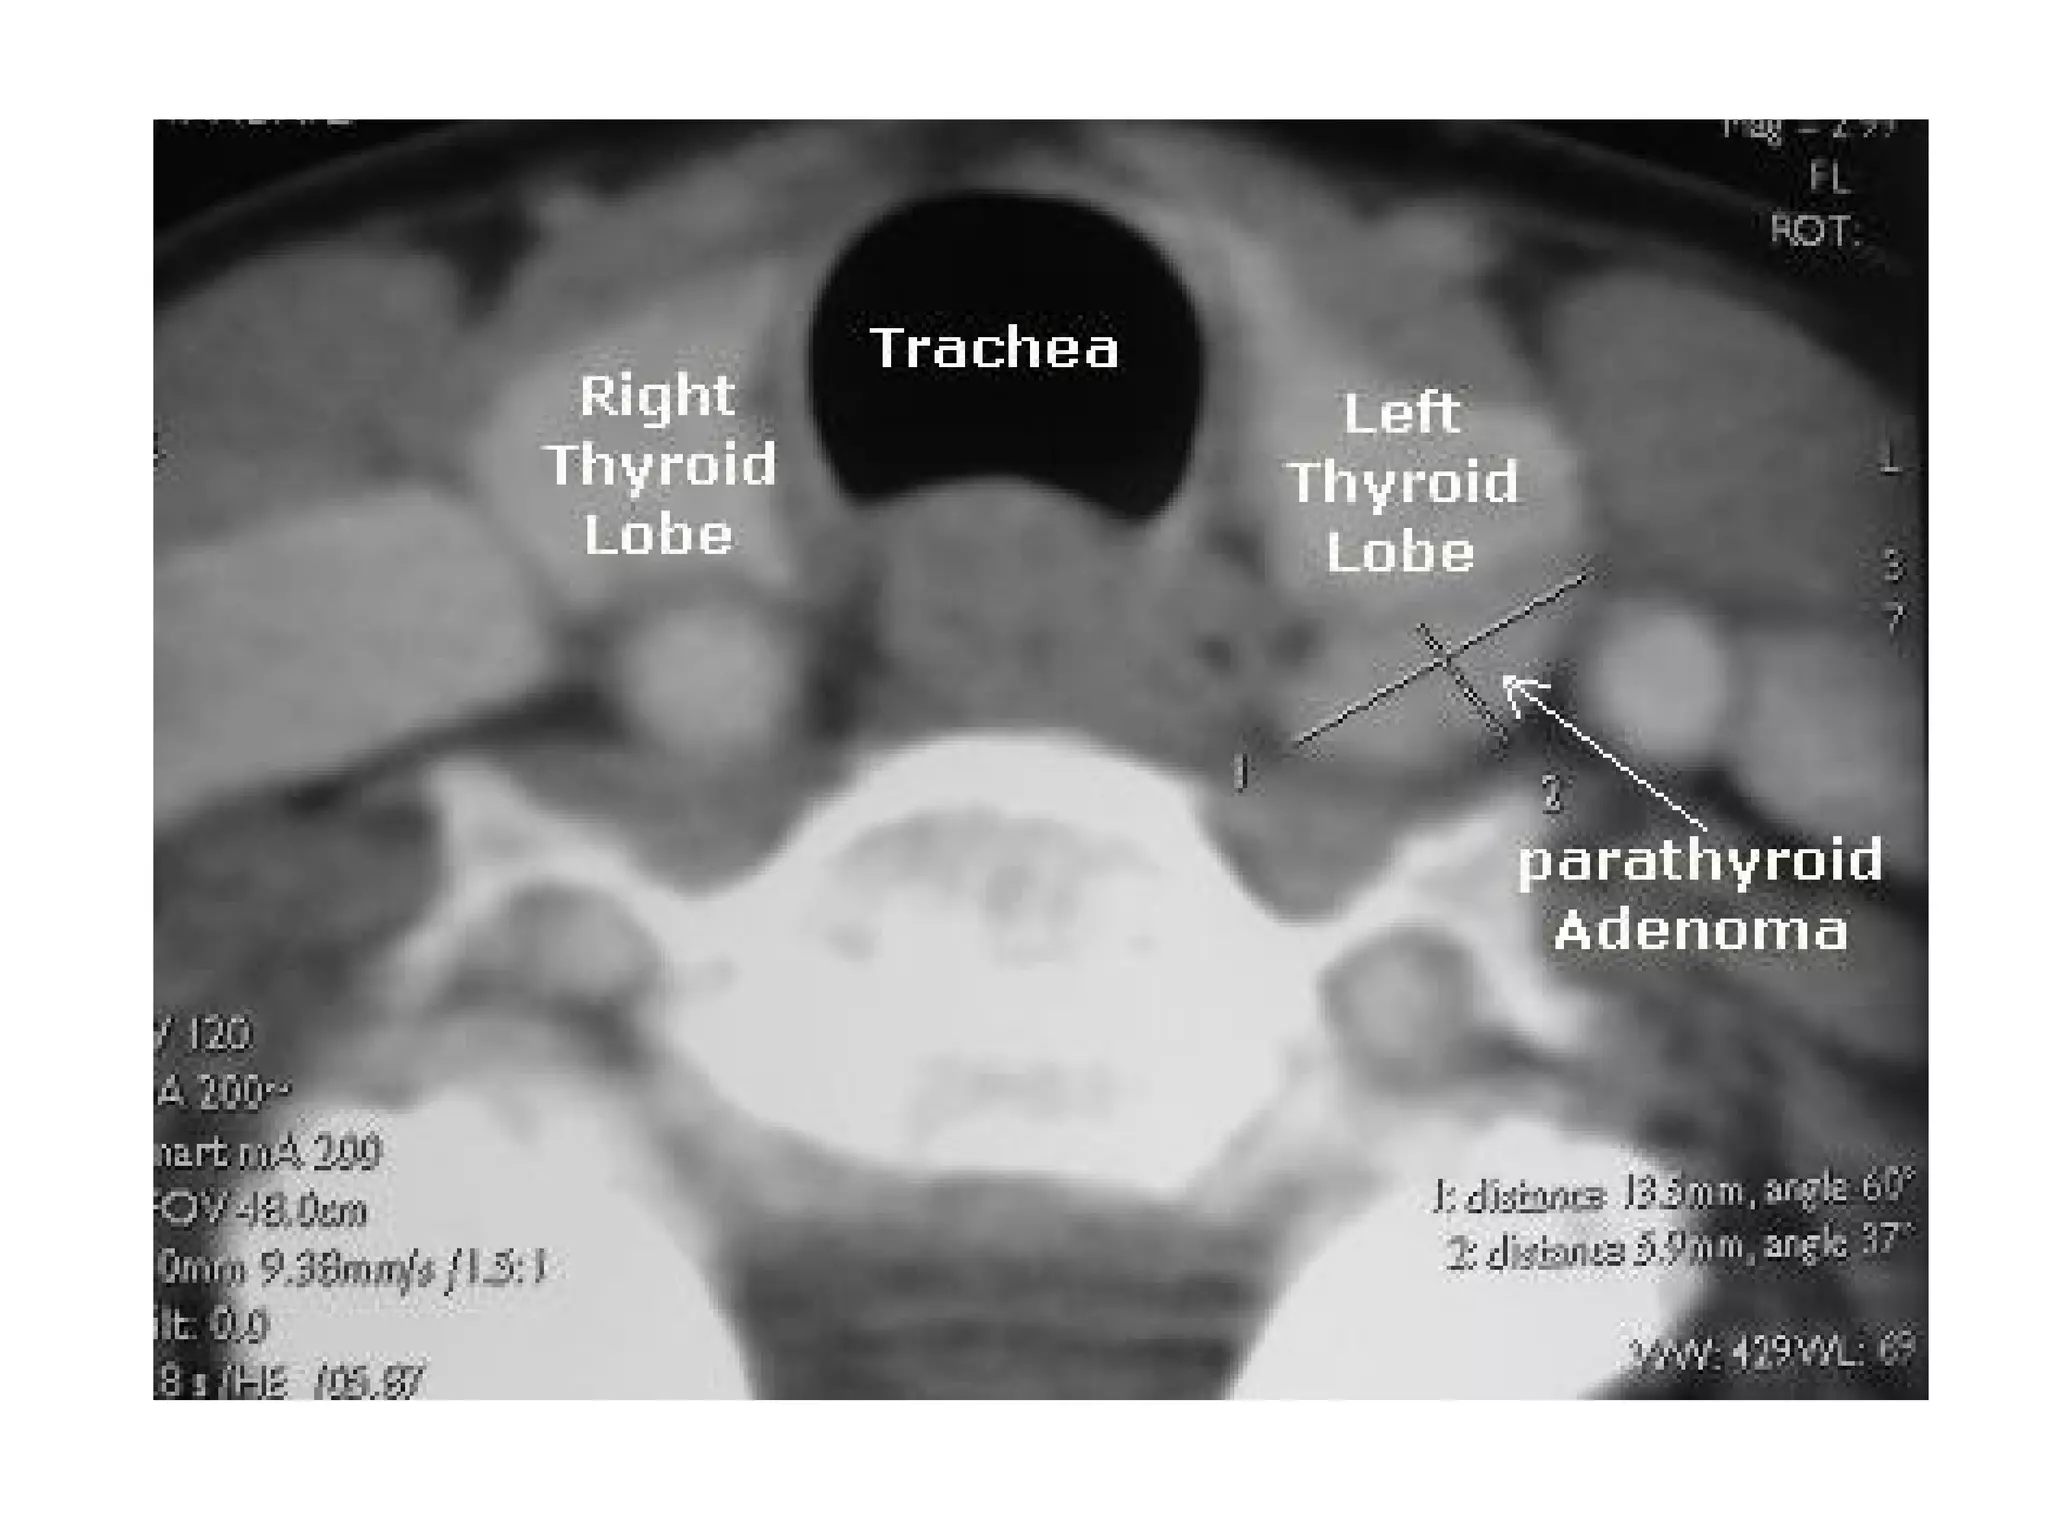

A 63-year-old woman with primary hyperparathyroidism, CT demonstrates

avidly enhancing lesions in the orthotopic superior location (arrows)

bilaterally with rapid washout of contrast greater than that of the adjacent

thyroid gland (A and D: noncontrast phase; B and E: initial postcontrast

“arterial” phase; C and F: delayed postcontrast phase), this patient

underwent bilateral exploration, and bilateral superior parathyroid adenomas

were found at surgery

A 63-year-old womanwith primary hyperparathyroidism, CT demonstrates avidly enhancing lesions in the orthotopic superior location (arrows) bilaterally with rapid washout of contrast greater than that of the adjacent thyroid gland (A and D: noncontrast phase; B and E: initial postcontrast “arterial” phase; C and F: delayed postcontrast phase), this patient underwent bilateral exploration, and bilateral superior parathyroid adenomas were found at surgery